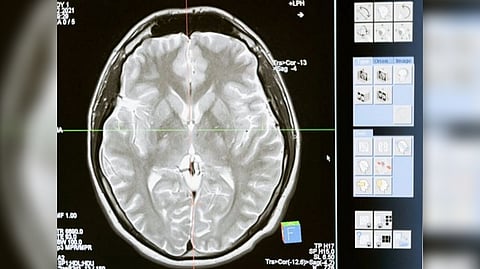

The cortex thickens markedly during this interval, and grows at an even faster pace in terms of surface area, by forming complicated cortical folds. Disruptions to cortical thickening and expansion in this phase have been linked to autism and schizophrenia. However, neuroscientists haven't had as detailed an understanding of this developmental phase as they would like. In particular, they've had a need for more comprehensive, high-resolution mapping, across the fetal-to-toddler age range, that divides or "parcellates" the developing cortex into distinct regions with their own growth rates -- especially surface area growth rates. In the study, Li and colleagues performed just such a mapping. They first gathered a set of 1,037 high-quality magnetic resonance imaging (MRI) scans of infants in the third-trimester-to-two-year age interval.

The scans came from two other research projects, the UNC/UMN Baby Connectome Project (BCP) and the Developing Human Connectome Project. The team analyzed the scan data using state-of-the-art, computer-based image-processing methods, essentially dividing the cortical surface into a virtual mesh containing thousands of tiny circular areas, and calculating the surface expansion rate for each of these areas.